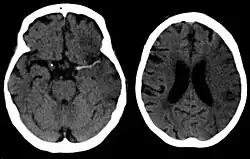

A CT showing early signs of a middle cerebral artery stroke with loss of definition of the gyri and grey white boundary

Dense artery sign in a patient with middle cerebral artery infarction shown on the left. Right image after 7 hours.

For diagnosing ischemic (blockage) stroke in the emergency setting:[77]

• CT scans (without contrast enhancements)

• MRI scan

For diagnosing hemorrhagic stroke in the emergency setting:

For detecting chronic hemorrhages, an MRI scan is more sensitive.[78]

CT scans may not detect ischemic stroke, especially if it is small, of recent onset,[10] or in the brainstem or cerebellum areas (posterior circulation infarct). MRI is better at detecting a posterior circulation infarct with diffusion-weighted imaging.[79] A CT scan is used more to rule out certain stroke mimics and detect bleeding.[10] The presence of leptomeningeal collateral circulation in the brain is associated with better clinical outcomes after recanalization treatment.[80] Cerebrovascular reserve capacity is another factor that affects stroke outcome – it is the amount of increase in cerebral blood flow after a purposeful stimulation of blood flow by the physician, such as by giving inhaled carbon dioxide or intravenous acetazolamide. The increase in blood flow can be measured by PET scan or transcranial doppler sonography.[81] However, in people with obstruction of the internal carotid artery of one side, the presence of leptomeningeal collateral circulation is associated with reduced cerebral reserve capacity.[82]